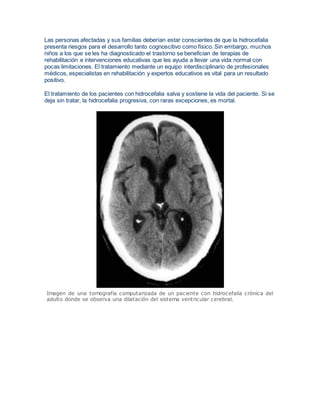

El tratamiento de los pacientes con hidrocefalia salva y sostiene la vida del paciente. Si se

Imagen de una tomografía computarizada de un paciente con hidrocefalia crónica del

adulto donde se observa una dilatación del sistema ventricular cerebral.